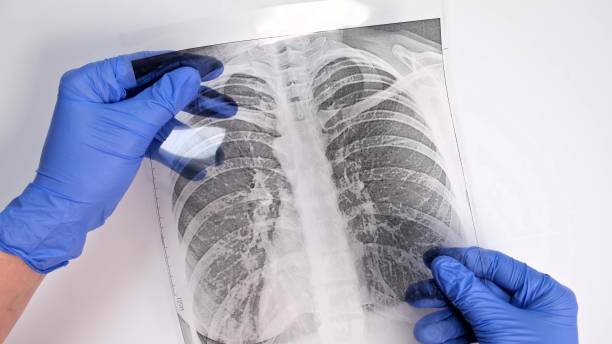

흉부 X-ray와 CT 검사

폐섬유증 초기에는 일반 흉부 X-ray에서 정상처럼 보일 수 있어 진단이 쉽지 않습니다. 그러나 고해상도 CT(High Resolution CT)를 통해 폐 조직의 섬유화 진행 정도를 더 정밀하게 확인할 수 있습니다. 따라서 폐섬유증 초기증상이 의심된다면 CT 검사가 중요합니다.